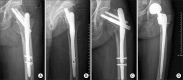

Methods: Eighty-two patients with intertrochanteric fractures that were treated with intramedullary hip nails between December, 2004 and January, 2011 were subjected to this study. The patients who could be followed for a minimum of one year postoperatively were enrolled. The immediate postoperative conditions were determined by radiograms: reduction status (3 parameters/4 points: contact accuracy of posteromedial cortex, severity of angulation, and distraction), fixation status (3 parameters/3 points: tip-apex distance, location of tip of the lag screw, entry point of the intramedullary nail), and fracture type (1 parameter/1 point: stable or unstable type by the Kyle's classification). Postoperative reduction loss and fixation failure were checked by radiograms taken at a minimum 3 months postoperative.

Results: Reduction loss and fixation failure were observed in 14 consecutive patients (17%). The fixation failure rate was 100% (2 patients) in score 1, 60% (3 out of the 5 patients) in score 2, 39% (3 out of the 8 patients) in score 3, and 50% (4 out of the 8 patients) in score 4 groups. There were fixation failures only in 1 out of 13 patients with score 5, and in 1 out of 18 patients with score 6. There was no fixation failure in 17 patients with score 7 and 11 patients with score 8.

Conclusions: Maintenance of the fracture reduction by the stable fixation in the patient scores over 5 could be predicted by the postoperative radiograms.